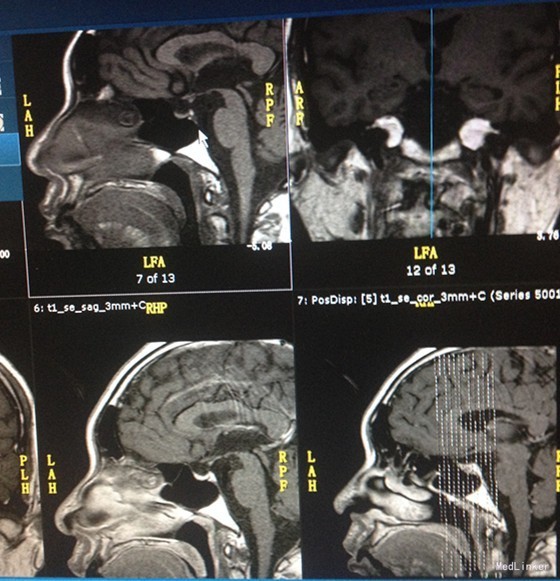

体格检查:胡须少,喉结小,阴毛呈倒三角型分布,阴毛稀少。阴茎牵长约5.5cm,宽约1.5cm,左侧睾丸约15ml、质软,右侧睾丸约10ml、质软,双侧睾丸无触痛。 辅助检查:鞍区MR平扫+增强:鞍上池下疝,垂体柄远端部分缺如。阴囊、双侧睾丸、附睾三维多普勒超声检查:双睾丸微石症,双睾丸鞘膜少量积液。甲状腺彩超:甲状腺回声稍低欠均匀,双颈部淋巴结显示。肾上腺CT平扫未见明显异常,胆囊结石,左肾结石。 检验结果:血脂分析:TG 2.00mmol/L,HDL-C 0.81mmol/L。甲功甲炎:FT4 8.9800pmol/L。男性激素系列:血清睾酮测定TES<0.69nmol/L,血清脱氢表雄酮及硫酸酯测定DHS1.04umol/L,血清游离睾酮F-TEST3.44pmol/L。促性腺激素系列:血清促卵泡刺激素测定FSH0.47mIU/mL,血清促黄体生成素测定LH<0.10mIU/mL。血清泌乳素测定PRL460.00mIU/L。OGTT试验未见明显异常。 戈那瑞林兴奋试验 -15分 0分 15分 30分 60分 90分 120分 LH(mIU/mL) <0.1 <0.1 1.3 1.6 1.34 0.98 0.87 FSH(mIU/mL) 0.52 0.51 0.86 1.19 1.38 1.28 1.34 肾上腺皮质激素系列 8:00 15:00 24:00 ACTH(10pg/ml) 24.10 18.27 10.52 COR (nmol/L) 75.83 62.54 30.28 胃复安兴奋试验 -30分 0分 30分 60分 120分 180分 催乳素 524.0 494.0 511.0 943.0 759.0 683.0 复查肾上腺皮质激素系列 8:00 15:00 ACTH(10pg/ml) 22.14 17.34 COR (nmol/L) 192.10 76.91 第二次戈那瑞林兴奋试验(皮下戈那瑞林4天后) -15分 0分 15分 30分 60分 90分 120分 LH(mIU/mL) 0.54 0.5 8.83 10.2 9.64 6.69 6.49 FSH(mIU/mL) 2.55 2.41 4.41 5.36 5.57 5.63 6.14 改良季氏法 6-9点 9-12点 12-15点 15-18点 18-21点 21-6点 尿渗透压 695 845 807 1010 800 507 尿比重 1.018 1.022 1.021 1.027 1.020 1.013 尿量 120 100 100 100 200 500 HCG兴奋试验 -15分 0分 24h 48h 72h 血清睾酮 <0.69 <0.69 2.27 5.82 3.85 血清雌二醇 <73.4 <73.4 <73.4 144.0 124.0

诊断:垂体前叶功能减退症 继发性性腺功能减退症 继发性肾上腺皮质功能减退症 继发性甲状腺功能减退症 鞍上池下疝 垂体柄远端部分缺如 高催乳素血症 血脂异常症 治疗:患者不同意行戈那瑞林泵治疗,要求皮下注射促性腺激素治疗。绒促素肌注,美百乐镇改善血脂,醋酸泼尼松片替代皮质激素治疗,优甲乐片替代甲状腺素治疗,溴隐亭口服